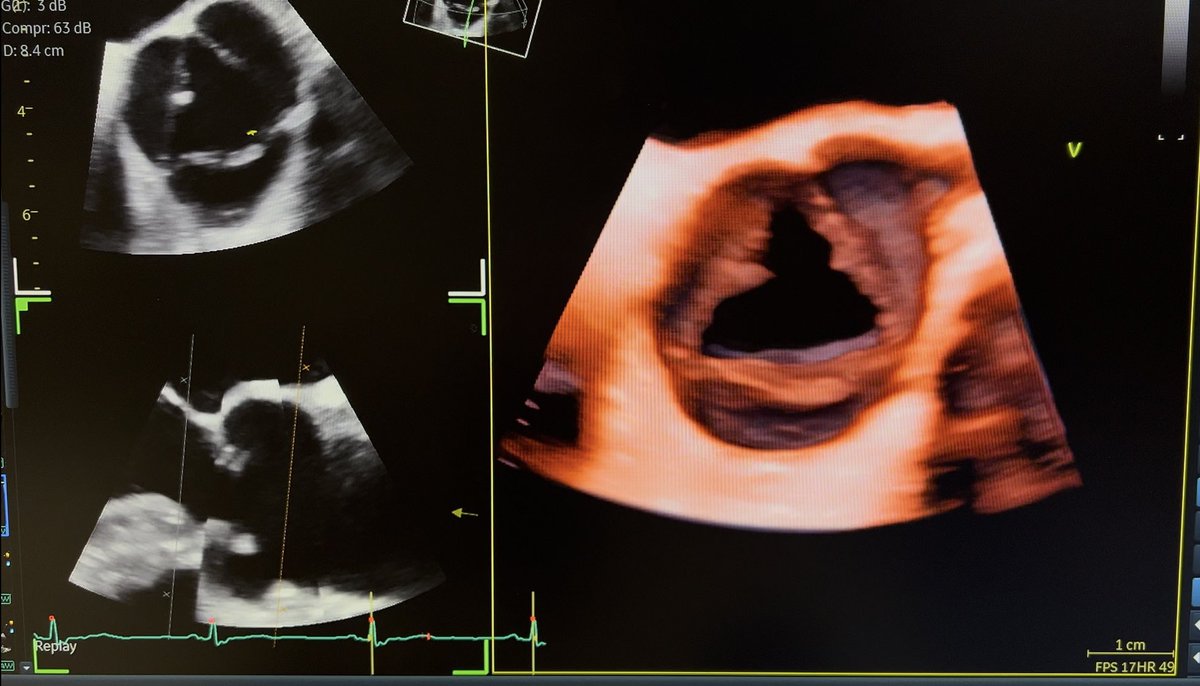

Another successful M-TEER in AFMR case by our team! Mild MR with 2 MitraClip devices! A dedicated session about guiding interventions will explain step-by-step TEER procedures during our 4D echo course! Register and advance your skills in 3DE! @lpbadano https://t.co/K8W7avBnj4

Another MitraClip case in AFMR case done successfully by our team! I am always happy to guide TEER cases!!@fiore_corrado @cardiopole @VDelgadoGarcia @denisamuraru @NAjmoneMarsan @drozgeozden @KemalogluOz @alexsfelixecho @NMerke @DonalErwan @lpbadano @echo_stepbystep @EchoSoliman